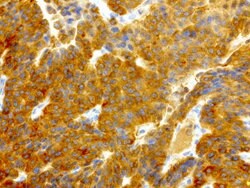

NME1 Mouse anti-Canine, Human, Rat, Clone: UMAB94, liquid, UltraMAB™

NME1 was identified because of its reduced mRNA transcript levels in highly metastatic cells. Nucleoside diphosphate kinase (NDK) exists as a hexamer composed of ′A′ (encoded by this gene) and ′B′ (encoded by NME2) isoforms. Mutations in the gene have been identified in aggressive neuroblastomas. Two transcript variants encoding different isoforms have been found for this gene. Co-transcription of this gene and the neighboring downstream gene (NME2) generates naturally-occurring transcripts (NME1-NME2), which encodes a fusion protein comprised of sequence sharing identity with each individual gene product.Specifications

| Immunocytochemistry, Immunofluorescence, Immunohistochemistry (Paraffin) | |